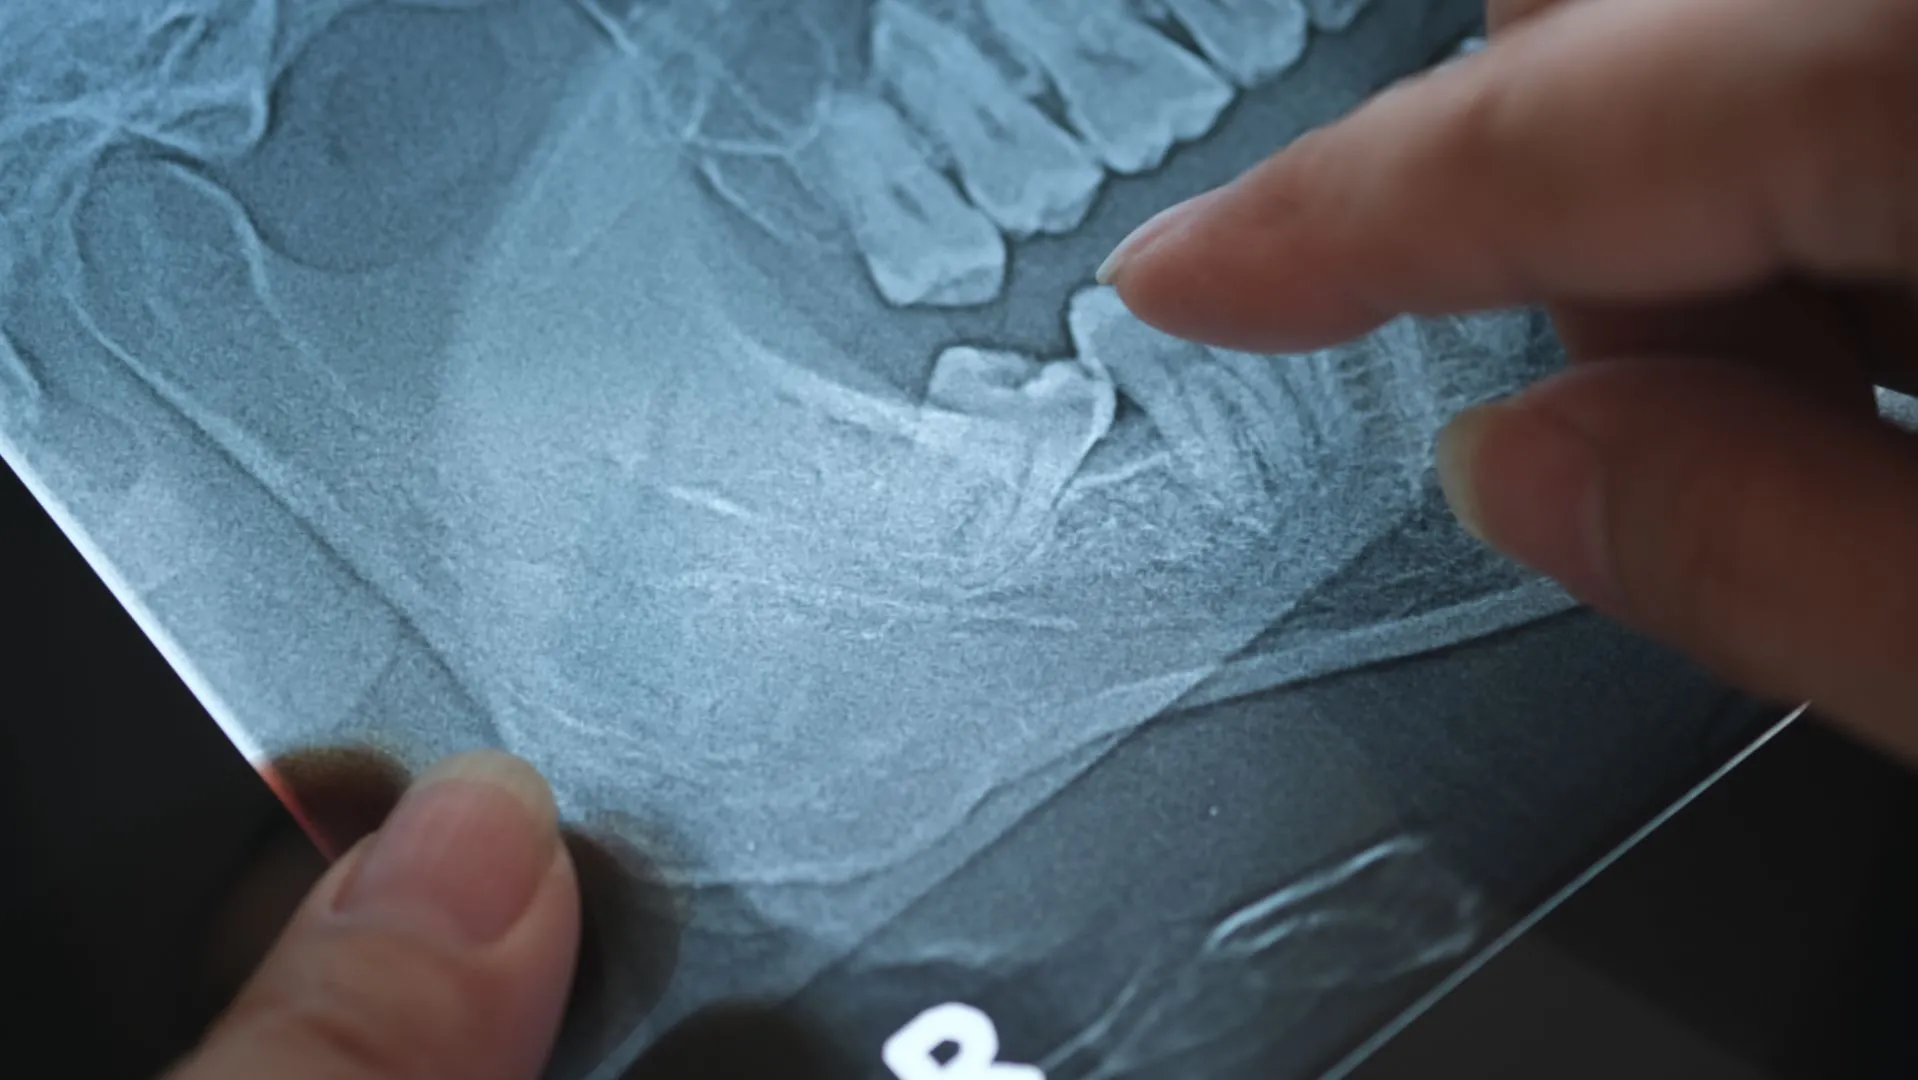

If you go to the dentist regularly (every six months) and wear your retainer, wisdom teeth should not cause problems for the rest of your mouth. Your dentist can track signs that your wisdom teeth are coming and use X-rays to determine when it’s time to remove them. But if you skip out on dental appointments, there is a chance your wisdom teeth could shift your aligned smile. Keep your eye out for any pain or swelling of the gums at the back of your mouth, as they are common signs your wisdom teeth are coming.

Armed with years of experience and imaging, your orthodontist will be able to keep a close eye on your wisdom teeth and let you know if it’s time for you to get them removed. Braces will not impact your surgery if you need to have your wisdom teeth removed. Like everyone else, you will have a routine procedure and go home with some painkillers and instructions to eat lots of soft foods (think: froyo, smoothies, and ice cream)!